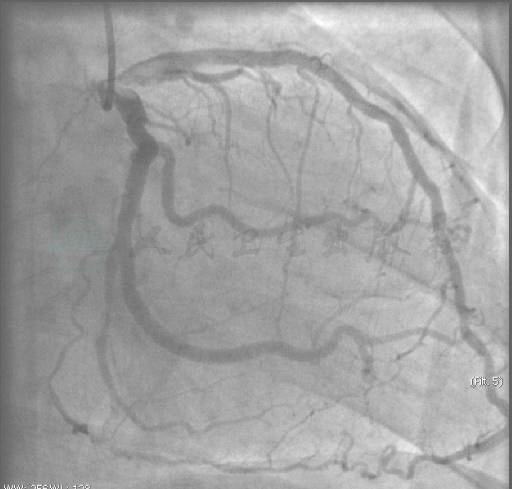

选用右侧桡动脉径路,6F血管鞘。造影发现:左主干短,前降支及回旋支原支架植入处未见明显狭窄,前降支通过穿隔支提供右冠远端TIMI 1~2级侧支血流;右冠远段闭塞(图1~图3)。

图1 造影可见良好前降支-间隔侧支至右冠远端